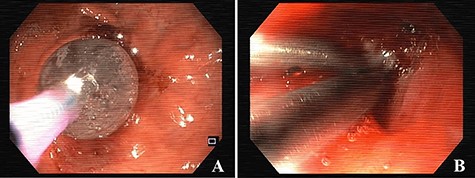

The stenosis of the GJA was dilated with a balloon and the proximal orifice of the GGF was closed with clips, endoscopically (see Fig. 3). Oral feeding was reintroduced with tolerance and the patient was discharged, 2 days after the procedure, medicated with oral proton pump inhibitors (PPIs).

Esophagogastroduodenoscopy images showing dilation of the gastro-jejunal anastomosis (A) and closure of gastro-gastric fistula with clips (B).